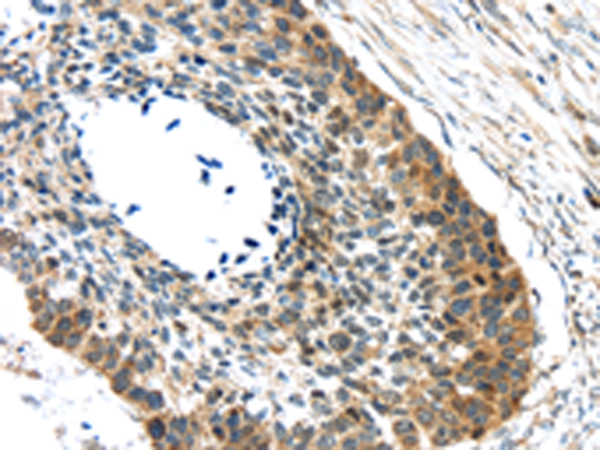

分类: 科研抗体货号: P11069别名: LKS; EPND; FESD; NR2A; GluN2A; NMDAR2A应用: IHC反应种属: Human, Mouse, Rat